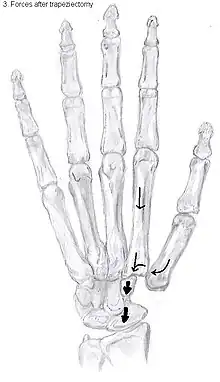

An empty gap is left by the trapeziectomy and the wound is closed with sutures. Despite this gap, no significant changes in function of the thumb are reported.[27] After the surgery, the thumb will be immobilized with a cast.

Trapeziectomy with tendon interposition

Some physicians still believe that it is better to fill the gap left by the trapeziectomy. They assume that filling the gap with a part of a tendon is preferable in terms of function, stability and position of the thumb. This is based on the assumption that interposition can help maintain the space between the metacarpal and the scaphoid, which will improve comfort and capability. Neither of these assumptions is supported by experimental evidence.

Trapeziectomy with ligament reconstruction

Another technique is used to reconstruct the volar beak ligament after trapeziectomy. The rationale is that ligament reconstruction(LR) helps maintain the gap between the metacarpal and the scaphoid, and that a larger gap is associated with greater comfort and capability.[32] Again these possibilities are not supported by experimental evidence.

Trapeziectomy with LRTI

Some physicians believe that combining LR with TI will help maintain gap between the metacarpal and the scaphoid.[33] And that doing so will improve comfort and capability. Keep in mind that these aspects of the rationale are not supported by experimental evidence. The evidence suggests that all of these procedures have comparable long-term results.